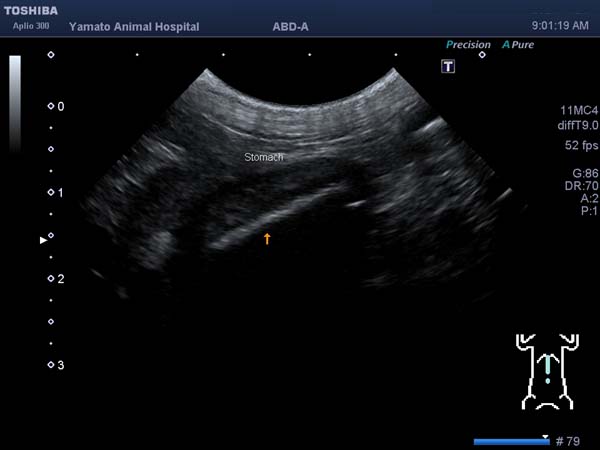

5~6歳以上の去勢手術をしていないオス犬に多い病気ですが、メス犬や去勢した犬に起こることもあります。お尻の筋肉が萎縮した結果、筋肉の隙間から直腸や膀胱が皮膚の下にとびでてしまいます。これにより便が出にくくなったり膀胱炎になったりします。手術をすることで機能回復および今後の致死的な状況を回避することができます。当院では去勢手術→結腸固定→前立腺固定→骨盤隔膜構成筋の縫縮→内閉鎖筋フラップ→浅臀筋フラップの順で通常腹側・臀部左右両側同時に行います。また老化以外に、筋肉が萎縮する原因があったり、腹圧がかかる原因があったりする場合も多いので、再発防止のためそれらの診断・治療も重要です。今回のワンちゃんも無事手術も終わり元気に退院しました。よかったね。